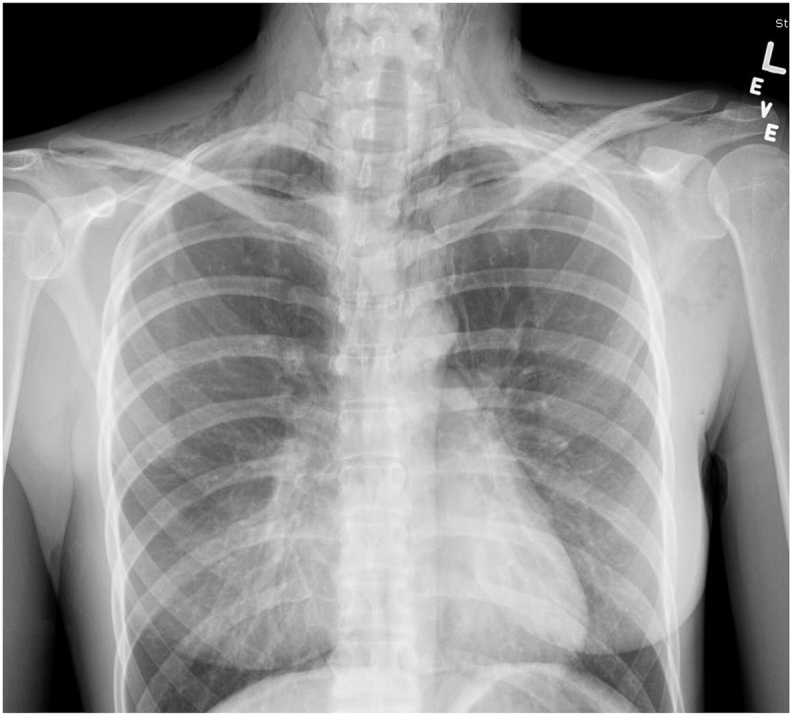

She had a white cell count of 18, 800/mm3, a hematocrit of 39% and a platelet count of 207,000/mm3. Her serum electrolytes, renal and liver function tests were all normal. Chest and neck radiograph revealed subcutaneous emphysema consistent with pneumomediastinum (Fig. 1).

Fig. 1.

Chest X-ray showing pneumomediastinum. The lungs are clear and there is no pneumothorax.